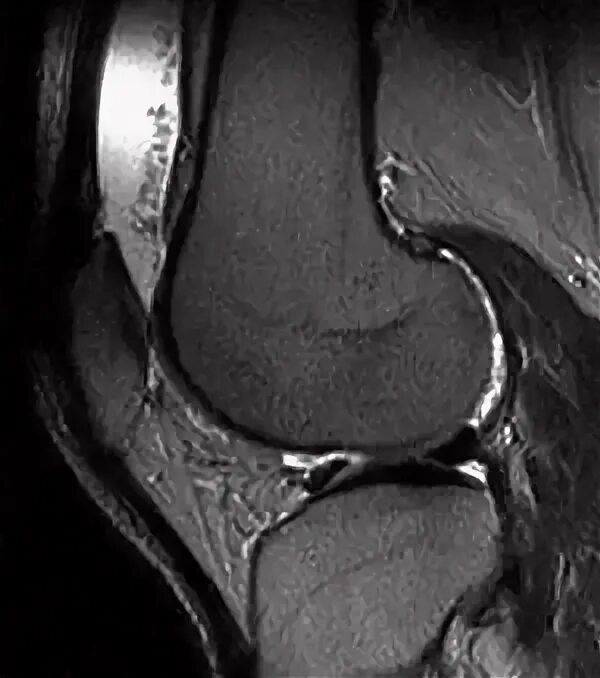

Минимально выраженный синовит